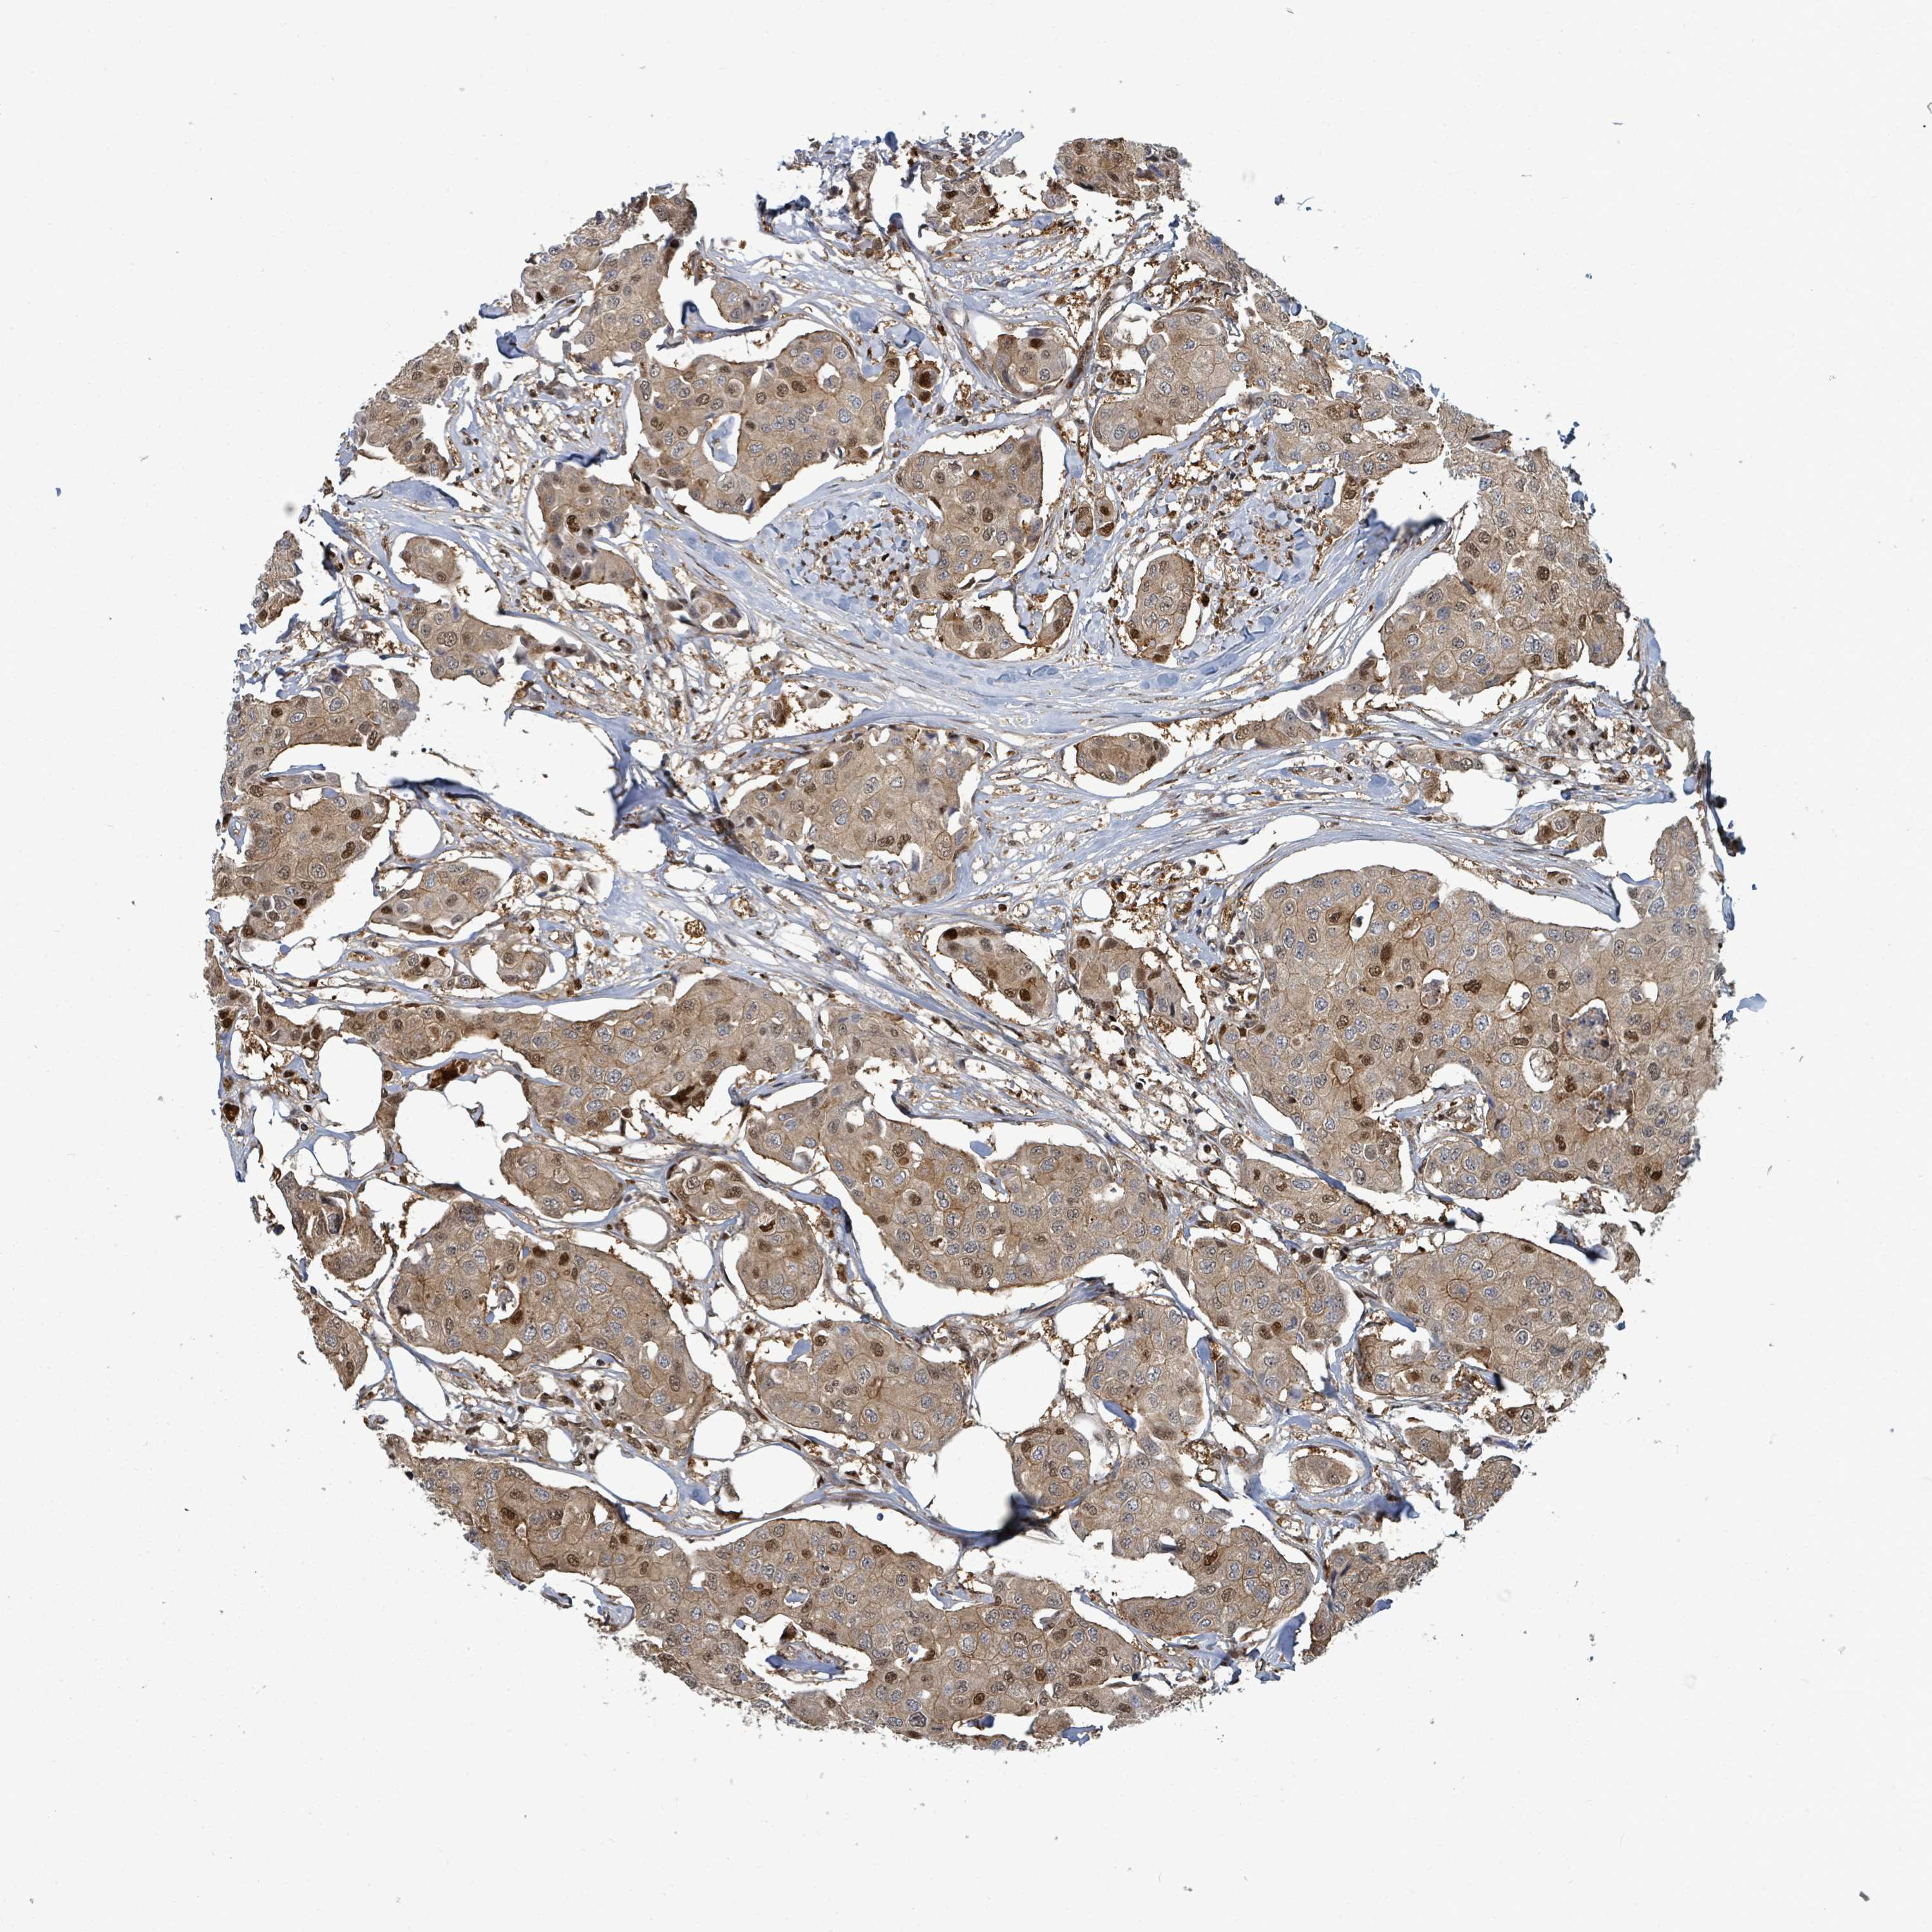

CANCER BREAST CANCER Show tissue menu

BRCA TCGA BRCA VALIDATION PROTEIN EXPRESSION